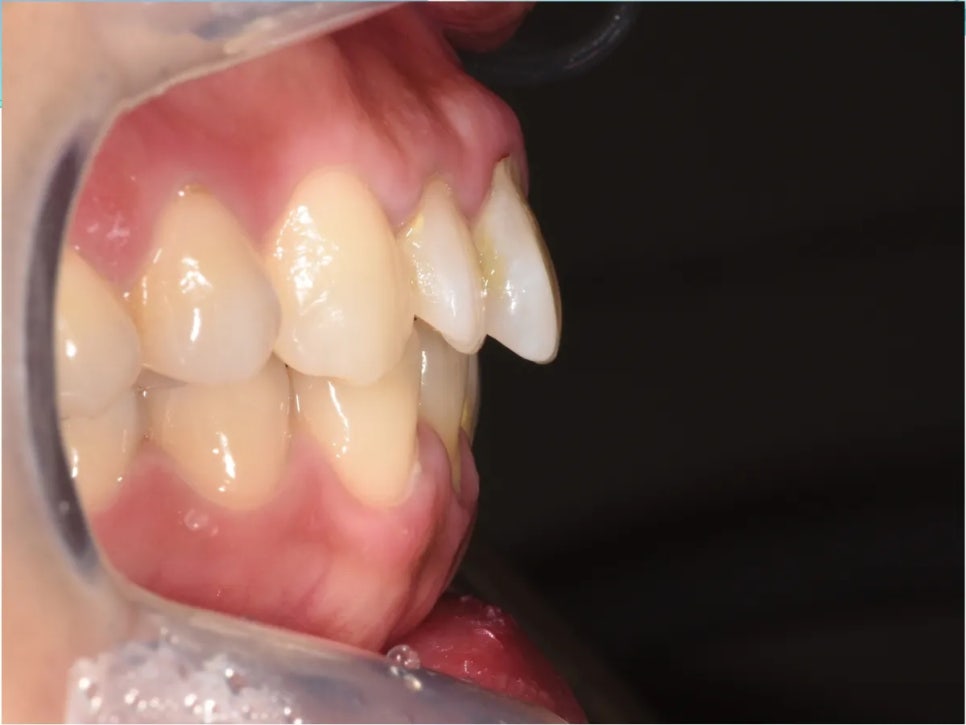

환자분이 가장 걱정하셨던 돌출입 역시 실제로 확인되었습니다. 옆에서 보면 위아래 앞니가 모두 앞쪽으로 기울어져 입이 돌출되어 보이는 상태였습니다.

측면에서 확인한 돌출입 상태